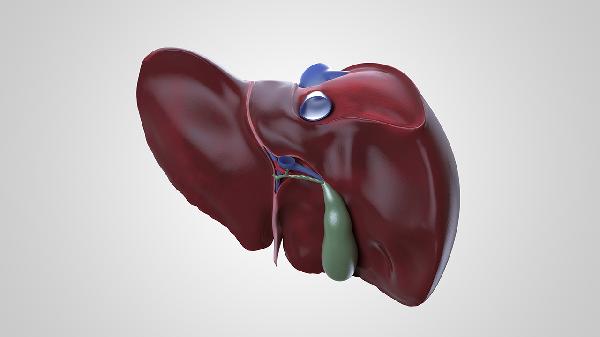

肝臟位于人體右上腹,大部分在右季肋區(qū)和腹上區(qū),小部分延伸至左季肋區(qū),是人體最大的實(shí)質(zhì)性器官。

肝臟右葉占據(jù)右季肋區(qū)主要空間,上界與膈肌相鄰,下緣通常不超過右側(cè)肋弓。該區(qū)域?qū)?yīng)體表投影在右側(cè)乳頭至肋弓連線范圍內(nèi),站立時(shí)因重力作用位置略有下移。肝臟右葉體積約占全肝三分之二,其解剖位置與膽囊、結(jié)腸肝曲關(guān)系密切。

二、腹上區(qū)

肝臟左葉跨越中線延伸至腹上區(qū),位于劍突下方與胃賁門相鄰。該區(qū)域肝臟前表面與腹前壁接觸,在消瘦人群或兒童群體中可能觸及肝緣。腹上區(qū)肝臟與胰腺頭部、十二指腸球部共同構(gòu)成重要的消化關(guān)聯(lián)結(jié)構(gòu)。

三、左季肋區(qū)

肝臟左葉末端延伸至左季肋區(qū),與胃底和脾臟毗鄰。此部分肝組織較薄,在影像學(xué)檢查中需注意與周圍臟器區(qū)分。左季肋區(qū)肝臟血供來自門靜脈左支和肝動(dòng)脈左支,靜脈回流通過肝左靜脈進(jìn)入下腔靜脈。

五、臟器鄰接

肝臟臟面與多個(gè)重要臟器接觸,右側(cè)與右腎和腎上腺相鄰,中部肝門區(qū)與膽總管、門靜脈關(guān)系緊密,后下緣與右腎靜脈水平相當(dāng)。這些密切的解剖關(guān)系使得肝臟疾病容易波及周圍器官。